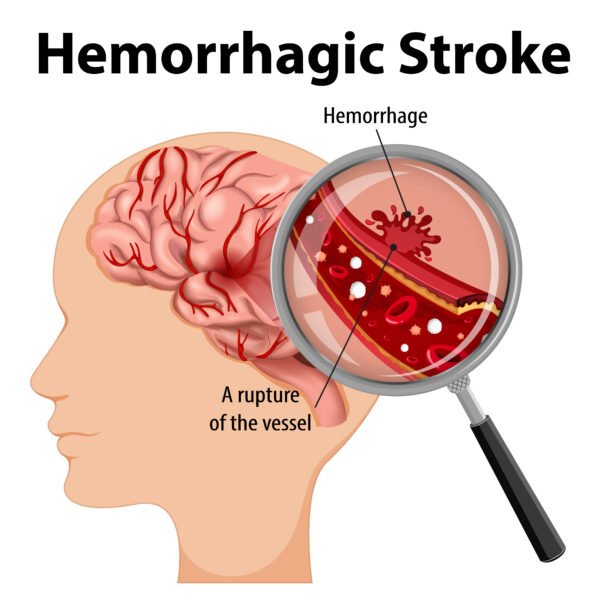

- Stroke